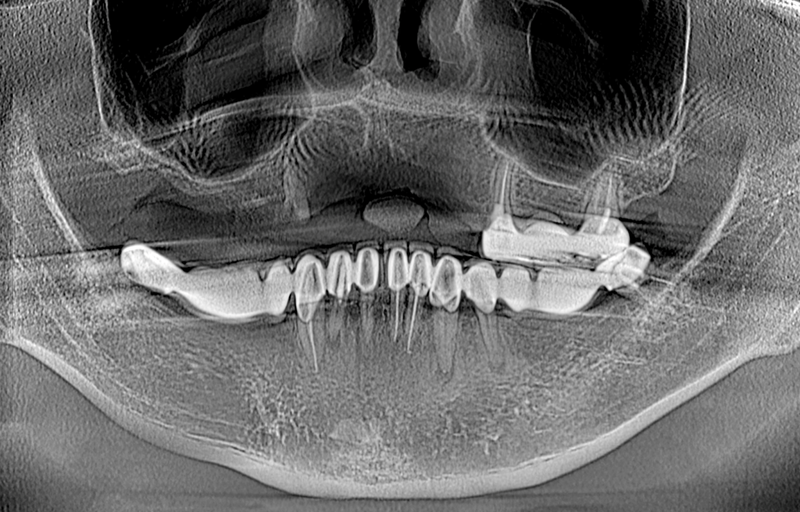

Tiêu xương hàm là hiện tượng xương ổ răng bị phá hủy khá nghiêm trọng. Hiện tượng này xuất hiện khi mật độ, chất lượng xương hàm bị suy giảm do nhiều nguyên nhân khác nhau, làm cho nướu bị teo lại, da mặt lão hóa, chảy xệ, ngày càng xuất hiện nhiều nếp nhăn và gây ảnh hưởng đến khớp cắn.

Tiêu xương hàm là hiện tượng xương ổ răng bị phá hủy khá nghiêm trọng